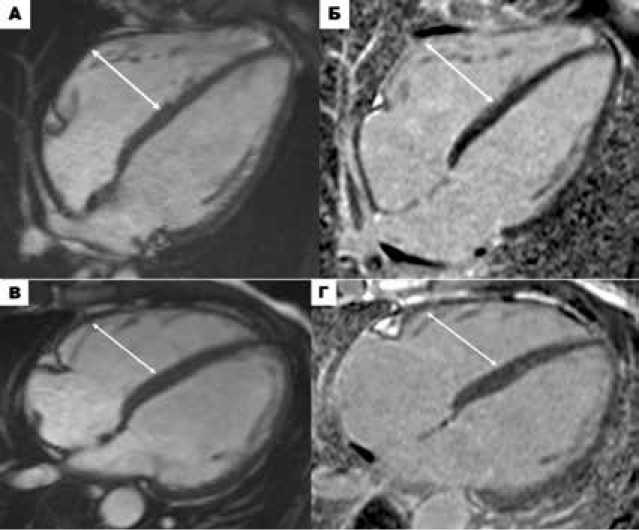

У пациента № 715 с отрицательным генотипом АКПЖ по данным МРТ сердца выявлены сниженная ФВ ПЖ (43%) без дилатации ПЖ (иКДО 38 мл/м 2 ) и микроаневризма ВТПЖ, синхронно сокращающаяся с миокардом ПЖ в систолу (рис. 2).

Рисунок 2. МРТ сердца пациента № 715. Кино-изображения сердца в проекции ВТПЖ в конечно-диастолическую фазу (А) и конечно-систолическую фазу (Б). Микроаневризма ВТПЖ (белые головки стрелок), синхронно сокращающаяся с миокардом ПЖ в систолу (врожденный анатомический вариант).

Figure 2. Cardiac MRI of patient №715. Cine images of the heart in the RVOT projection during the end-diastolic phase (A) and end-systolic phase (Б). RVOT microaneurysm (white arrowheads) contracting synchronously with the RV myocardium during systole (congenital anatomical variant).

У 9 пациентов присутствовали лишь один из малых критериев АКПЖ (региональный дискинез/акинез стенки ПЖ) без очевидных структурных изменений ПЖ или дилатации ПЖ (табл. 6). Ложноположительная интерпретация регионального дискине-за/акинеза стенок ПЖ на МРТ была наиболее частой ошибкой, которая наблюдалась у данных пациентов. Так, у пациентки № 766 обнаружен дивертикул под апикальным выпячиванием ПЖ, связанный с модераторным пучком, который привел к невер- ному истолкованию регионального дискинеза стенок ПЖ (рис. региональным дискинезом стенок ПЖ на МРТ (рис. 3В-Г) при-3А-Б). У пациента № 1м с воронкообразной грудной клеткой и сутствовала частая ЖЭC и неустойчивая ЖТ.

Рисунок 3. А-Б. МРТ сердца пациента № 766. А. Кино-изображение сердца в четырёхкамерной проекции в конечно-систолическую фазу. Б. Изображение сердца в четырёхкамерной проекции в конечно-диастолическую фазу в последовательности с отсроченным контрастным усилением. Дивертикулоподобное апикальное выпячивание ПЖ, связанное анатомически с модераторным пучком – врожденный анатомический вариант (белые головки стрелок). В-Г. МРТ сердца пациента № 1м: В. Изображение сердца в темнокровной последовательности HASTE («dark blood»). Г. Изображение сердца в последовательности с отсроченным контрастным усилением. Вариант анатомии грудной клетки (Pectus excavatum) с компрессией грудиной свободной стенки ПЖ (белые головки стрелок).

Figure 3. A-Б. Cardiac MRI of patient №766. A. Cine image of the heart in the four-chamber projection in the end-systolic phase. Б. Image of the heart in the four-chamber projection in the end-diastolic phase in a sequence with delayed contrast enhancement. A diverticulum-like apical protrusion of the right ventricle, anatomically associated with the moderator bundle, is a congenital anatomical variant (white arrowheads). В-Г. Cardiac MRI of patient #1m: В. Image of the heart in a HASTE ("dark blood") sequence. Г. Image of the heart in a sequence with delayed contrast enhancement. Variant chest anatomy (pectus excavatum) with compression of the free wall of the right ventricle by the sternum (white arrowheads).